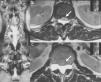

Clinical caseA 67-year-old male with a history of type 2 diabetes mellitus and lower back pain irradiating to both legs, predominantly the right, neurogenic claudication of both legs and weakness in both feet for 15 months. Physical examination revealed hypoesthesia in the right L5 dermatome, increased myotatic reflexes in both legs with Babinski sign and 4/5 power in the psoas and quadriceps bilaterally. Central and lateral stenosis of the spinal canal could be seen on magnetic resonance imaging at lumbar level from L3-L4, L4-L5, as well as the presence of a cystic lesion with regular limits, from T12 to L2. The lesion was hypointense in T1-weighting and hyperintense in T2-weighting, characteristically homogeneous with the cerebrospinal fluid; no contrast enhancement was observed on the MRI (Fig. 1). The compression of the conus medullaris and the dural sac was notable in T12-L1 and L1-L2 respectively and bilateral foraminal stenosis (Fig. 2), at the same levels due to expansion of the cyst. Given these signs, we decided to perform an evacuatory lumbar puncture targeting the spinal extradural cyst in space L1-L2 guided by fluoroscopy (Fig. 3), in order to decompress the nerve elements on which the cyst had an expansive effect. After the procedure, the patient's myelopathic syndrome improved, he had normal osteotendinous reflexes in both legs, and there were no bilateral Babinski reflexes. However, the patient continued to have neurogenic claudication and radicular pain in both legs, therefore one month after the evacuatory puncture a minimally invasive approach with microscope and tubular retractor system was undertaken through the midline for segments L3-L4 and L4-L5, and the narrow lumbar canal was decompressed. This achieved complete improvement of his symptoms.

(A) T2-weighted coronal section magnetic resonance image showing the foraminal extension of the cyst (asterisk) in T12-L1 and L1-L2. (B) T2-weighted axial section magnetic resonance image of level T12 showing ventral displacement of the conus medullaris (arrow) caused by the cyst. (C) T2-weighted axial section magnetic resonance image of level L1 showing compression of the cauda equina (arrow) caused by the cyst.